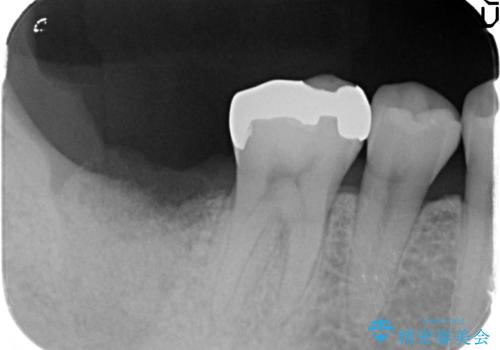

X線写真より根尖付近までの骨吸収を認めます。

抜歯を余儀なくされる状況ですが、将来的にインプラントによる咬合機能回復を希望されたので抜歯と同時に骨補填剤を填入し骨の造成をしたのちのインプラント治療を計画します。

歯を失い、将来的にインプラントを埋入し咬合機能を回復していく場合、十分な骨量の確保は重要です。

今回抜歯後、骨が十分に確保できないとの判断から抜歯と同時に骨補填剤の填入を行いました。